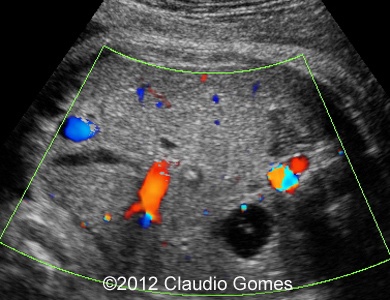

Images 8-11: Persistent right umbilical vein and Inferior vena cava interruption with continuity of the flow via Azygos vein on grayscale and color Doppler

Fig8

Fig9

Fig10

Fig11